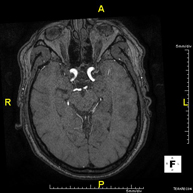

- RM Cerebral (craneal)

Prueba diagnóstica no invasiva que consiste en la obtención de imágenes de alta definición anatómica del cerebro mediante el empleo de un campo electromagnético y ondas de radio (con un emisor y un receptor). No utiliza radiación ionizante. Indicaciones: problemas vasculares, pérdida de memoria, epilepsia, cefalea, malformaciones, sospecha de tumor, meningitis. - RM Cais